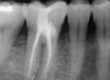

Rx. Control